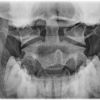

Dens

index.png

Indikation

Fraktur

Lagerung

Rückenlage

Kinn anziehen, bis obere Zahnreihe und Hinterhauptshöcker senkrecht zueinanderstehen

Mund weit geöffnet

Zentralstrahl

Querstrahl: Mundwinkel

Längsstrahl: Medianebene

Einblendung

seitlich ca. 1 QF neben Mundwinkel,

cranial: Spina nasalis

Bemerkung

auch sitzend am Stativ möglich

Qualitätskriterien

Bissebene und Unterkante des Hinterhaupts sollen sich überdecken. Der Dens ist mittelständig: gleicher Abstand zum aufsteigenden Ast des Unterkiefers beidseits. Weitgehend überlagerungsfreie Darstellung des Atlas und des Axis mit Dens. Gut einsehbares Atlantookzipital- und Atlantoaxialgelenk. Der vordere und der hintere Atlasbogen überlagern den Dens.